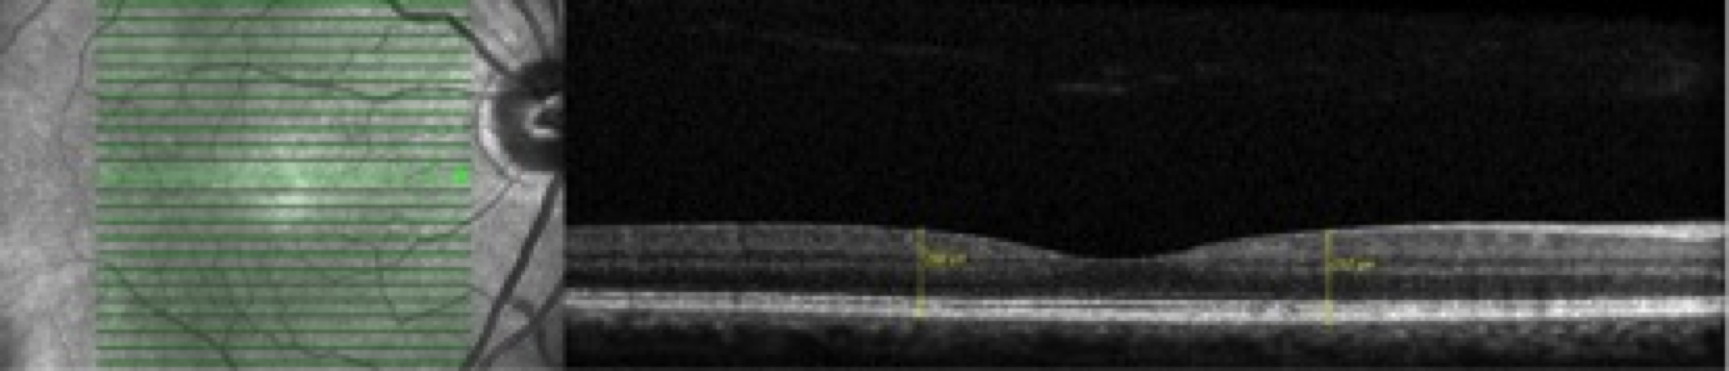

Objectivos: Um dos efeitos secundários dos anti-maláricos é o desenvolvimento de retinopatia, com consequente perda irreversível da visão, sendo o adelgaçamento retiniano um sinal precoce. Uma vez que o ERGmf foi proposto como exame de detecção desta retinopatia mas não está amplamente disponível, o objectivo foi verificar o papel do SD-OCT na avaliação da toxicidade retiniana precoce dos anti-maláricos. Métodos: estudo prospectivo com 58 doentes (116 olhos), entre Março-Junho 2014, divididos em 3 grupos: 1 (controlo, n=11), 2 (olhos com sinais de toxicidade no ERGmf, n=17) e 3 (olhos expostos a anti-maláricos mas sem alterações no ERGmf, n=30). A espessura retiniana foi medida (mm) a 1.0 mm temporal e nasal ao centro da fóvea com SD-OCT. Análise estatística: software STATA 13.0. Resultados: O teste t demonstrou diferenças estatisticamente significativas entre a média da espessuras retiniana dos grupos 1 (337.66±12.93) e 2 (320.97±16.77), t(26)=2.80, p=0.01, grupos 1 (337.66±12.93) e 3 (348.02±11.78), t(39)=-2.43 e p<0.001 e grupos 2 (320.97±16.77) e 3 (348.02±11.78), t(45)=-6.47 e p<0.001; α=0.05. No grupo 2, a espessura retiniana a 1.0 mm nasal (313.62±17.32) à fóvea foi estatisticamente inferior à espessura a 1.0 mm temporal (328.32±17.54), t(32)=-2.46, p=0.02, α=0.05. Conclusões: Os doentes do grupo 2 demonstraram menor espessura retiniana total do que os do grupo 3. A menor espessura retiniana a 1 mm nasal à fóvea do que na região correspondente temporal pode indicar dano precoce às células ganglionares. O SD-OCT pode ser uma ferramenta útil na avaliação do dano retiniano dos anti-maláricos.